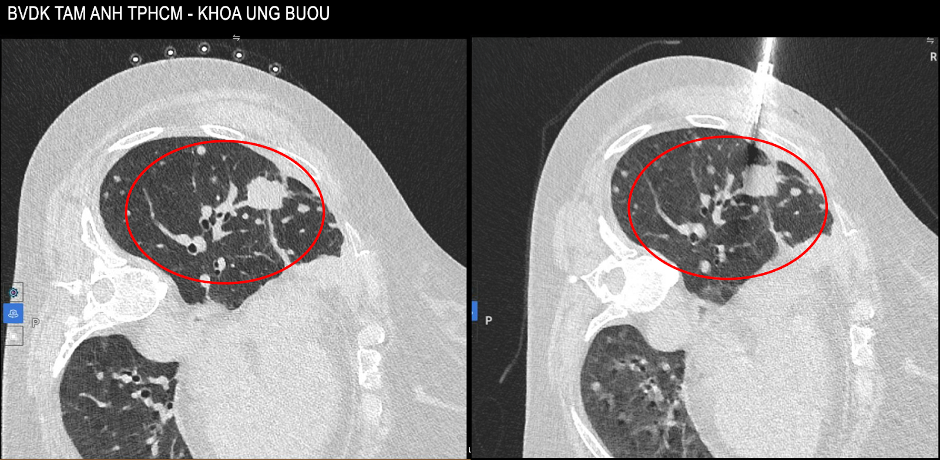

A CT image from 10/2025 showed the tumor increased to 4 cm and scattered lesions surrounding it. *Photo: Tam Anh General Hospital* |

Her chest pain worsened. A CT scan in 10/2025 revealed the lesion had increased to 4 cm. Doctors ordered a lung tumor biopsy to identify drug-resistant gene mutations. Histopathology and immunohistochemistry results after two biopsies revealed a T790M mutation on the EGFR gene and several other mutations on the mTOR and TP53 genes, increasing the complexity of her condition.